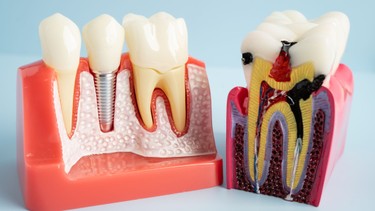

Viêm tủy răng là tình trạng viêm nhiễm xảy ra ở mô tủy nằm bên trong răng, nơi chứa các mạch máu và dây thần kinh có chức năng nuôi dưỡng và dẫn truyền cảm giác. Ở trẻ em, viêm tủy thường xảy ra ở răng sữa do sâu răng tiến triển hoặc chấn thương răng. Tủy răng bị viêm có thể hồi phục nếu được điều trị sớm, nhưng nếu để lâu sẽ dẫn đến hoại tử, gây đau dữ dội và ảnh hưởng đến cấu trúc răng vĩnh viễn sau này.

Viêm tủy răng ở trẻ em chủ yếu bắt nguồn từ các tổn thương răng kéo dài mà không được điều trị đúng cách. Tủy răng là mô sống nằm sâu bên trong răng, rất nhạy cảm với các tác nhân gây hại từ bên ngoài. Khi lớp men và ngà răng bị phá hủy, vi khuẩn dễ dàng xâm nhập vào tủy, gây viêm nhiễm và hoại tử.